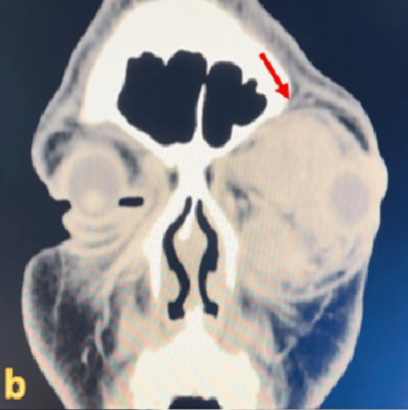

사진=Cureus 캡처.

CT 촬영 결과, 시신경을 심하게 누르고 있는 큰 종양이 발견됐다. 이후 제거 수술을 받았으나, 이미 손상된 시신경은 회복되지 않았다.